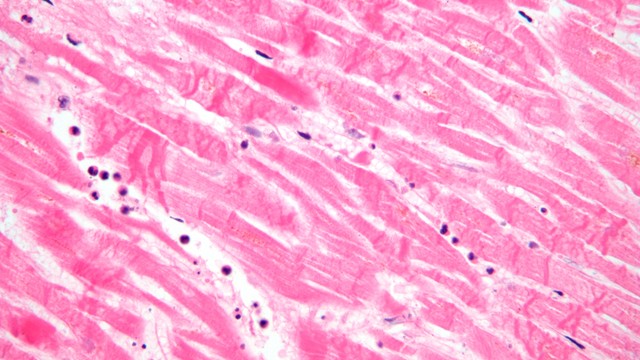

/https://cms-prod.s3-sgn09.fptcloud.com/histopathology_la_gi_tam_quan_trong_cua_histopathology_mo_benh_hoc_2caf048a2a.jpg)

Histopathology hay mô bệnh học liên quan đến việc sử dụng kính hiển vi kiểm tra mô để nghiên cứu những biểu hiện của bệnh. Nói cách khác, histopathology là nghiên cứu các mô liên quan đến bệnh tật, rất cần thiết cho việc chẩn đoán nhiều bệnh ung thư. Hãy cùng Nhà thuốc Long Châu tìm hiểu histopathology là gì ở bài viết dưới đây nhé.